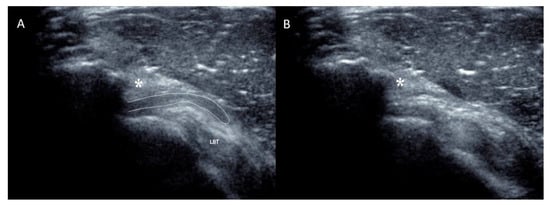

The nine patients included in this study (Figure 3) presented non-traumatic painful snapping syndrome without plication before the snap upon dynamic sonography (Figure 4A,B and video available in Supplementary Materials).

Figure 4.

Sagittal view of the shoulder along the anterior edge of the acromion as demonstrated in Figure 1. (A) During slight antepulsion of the shoulder, the anterior recess of the subacromial bursa is visible between the coracoacromial ligament (asterisk) and the deltoid muscle superficially and the rotator interval and long bicep tendon (LBT) in a deeper position. (B) During retropulsion of the shoulder, anterior recess of the subacromial moves backward and suddenly disappears underneath the coracoacromial ligament and neighboring acromion, thus provoking an audible snap.